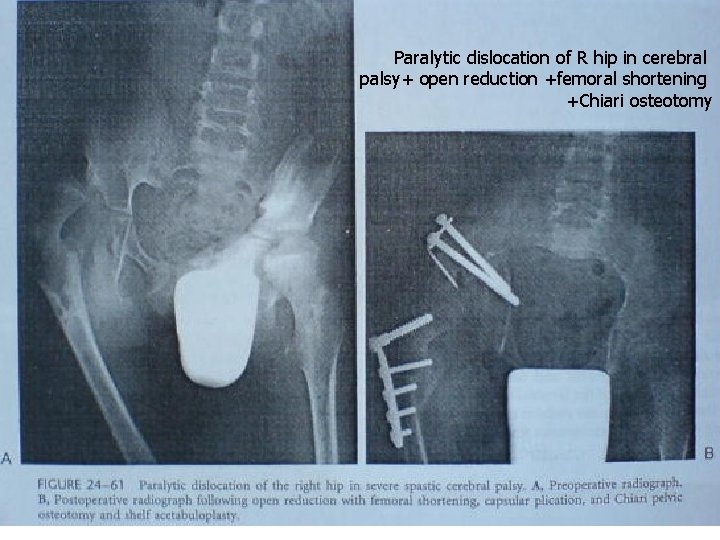

Paralytic dislocation of R hip in cerebral palsy+ open reduction +femoral shortening +Chiari osteotomy

Combined femoral varus and pelvic osteotomies. . The Chiari osteotomy. This osteotomy is performed by making a horizontal osteotomy from the sciatic notch to a point just at the superolateral margin of the acetabulum. and the osteotomy is displaced medially so that the hip capsule lies over the lateral bony surface of the ilium. Indications for Chiari osteotomy were: l l Presence of severe subluxation or, The presence of moderate incongruity on arthrography following the femoral osteotomy.

Combined femoral varus and pelvic osteotomies In cases in which a femoral VDRO does not provide adequate coverage or stability to the hip, pelvic osteotomy should be performed. The pelvic osteotomies used are. . l Re directional osteotomies (such as the Steel an Salter procedures) l Osteotomies that reshape the acetabulum (such as Pemberton and Dega osteotomies) l Salvage osteotomies that increase the area of the acetabulum with non articular cartilage (such as the Chiari osteotomy and the shelf augmentation procedure. The two pelvic procedures with the longest historical use in patients with cerebral palsy are the Chiari osteotomy and the shelf augmentation procedure. .